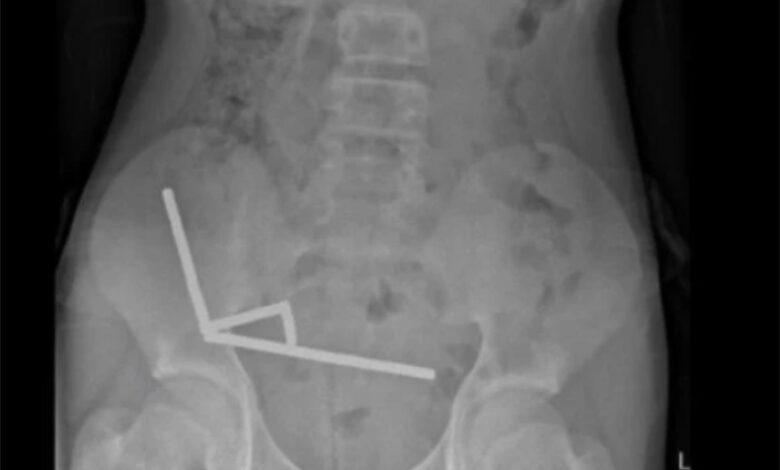

Ele foi internado após quatro dias de dores abdominais e exames de imagem mostraram correntes de ímãs aderidas entre diferentes partes do intestino, unidas pela força magnética. O contato prolongado causou necrose por pressão e risco de perfuração intestinal.